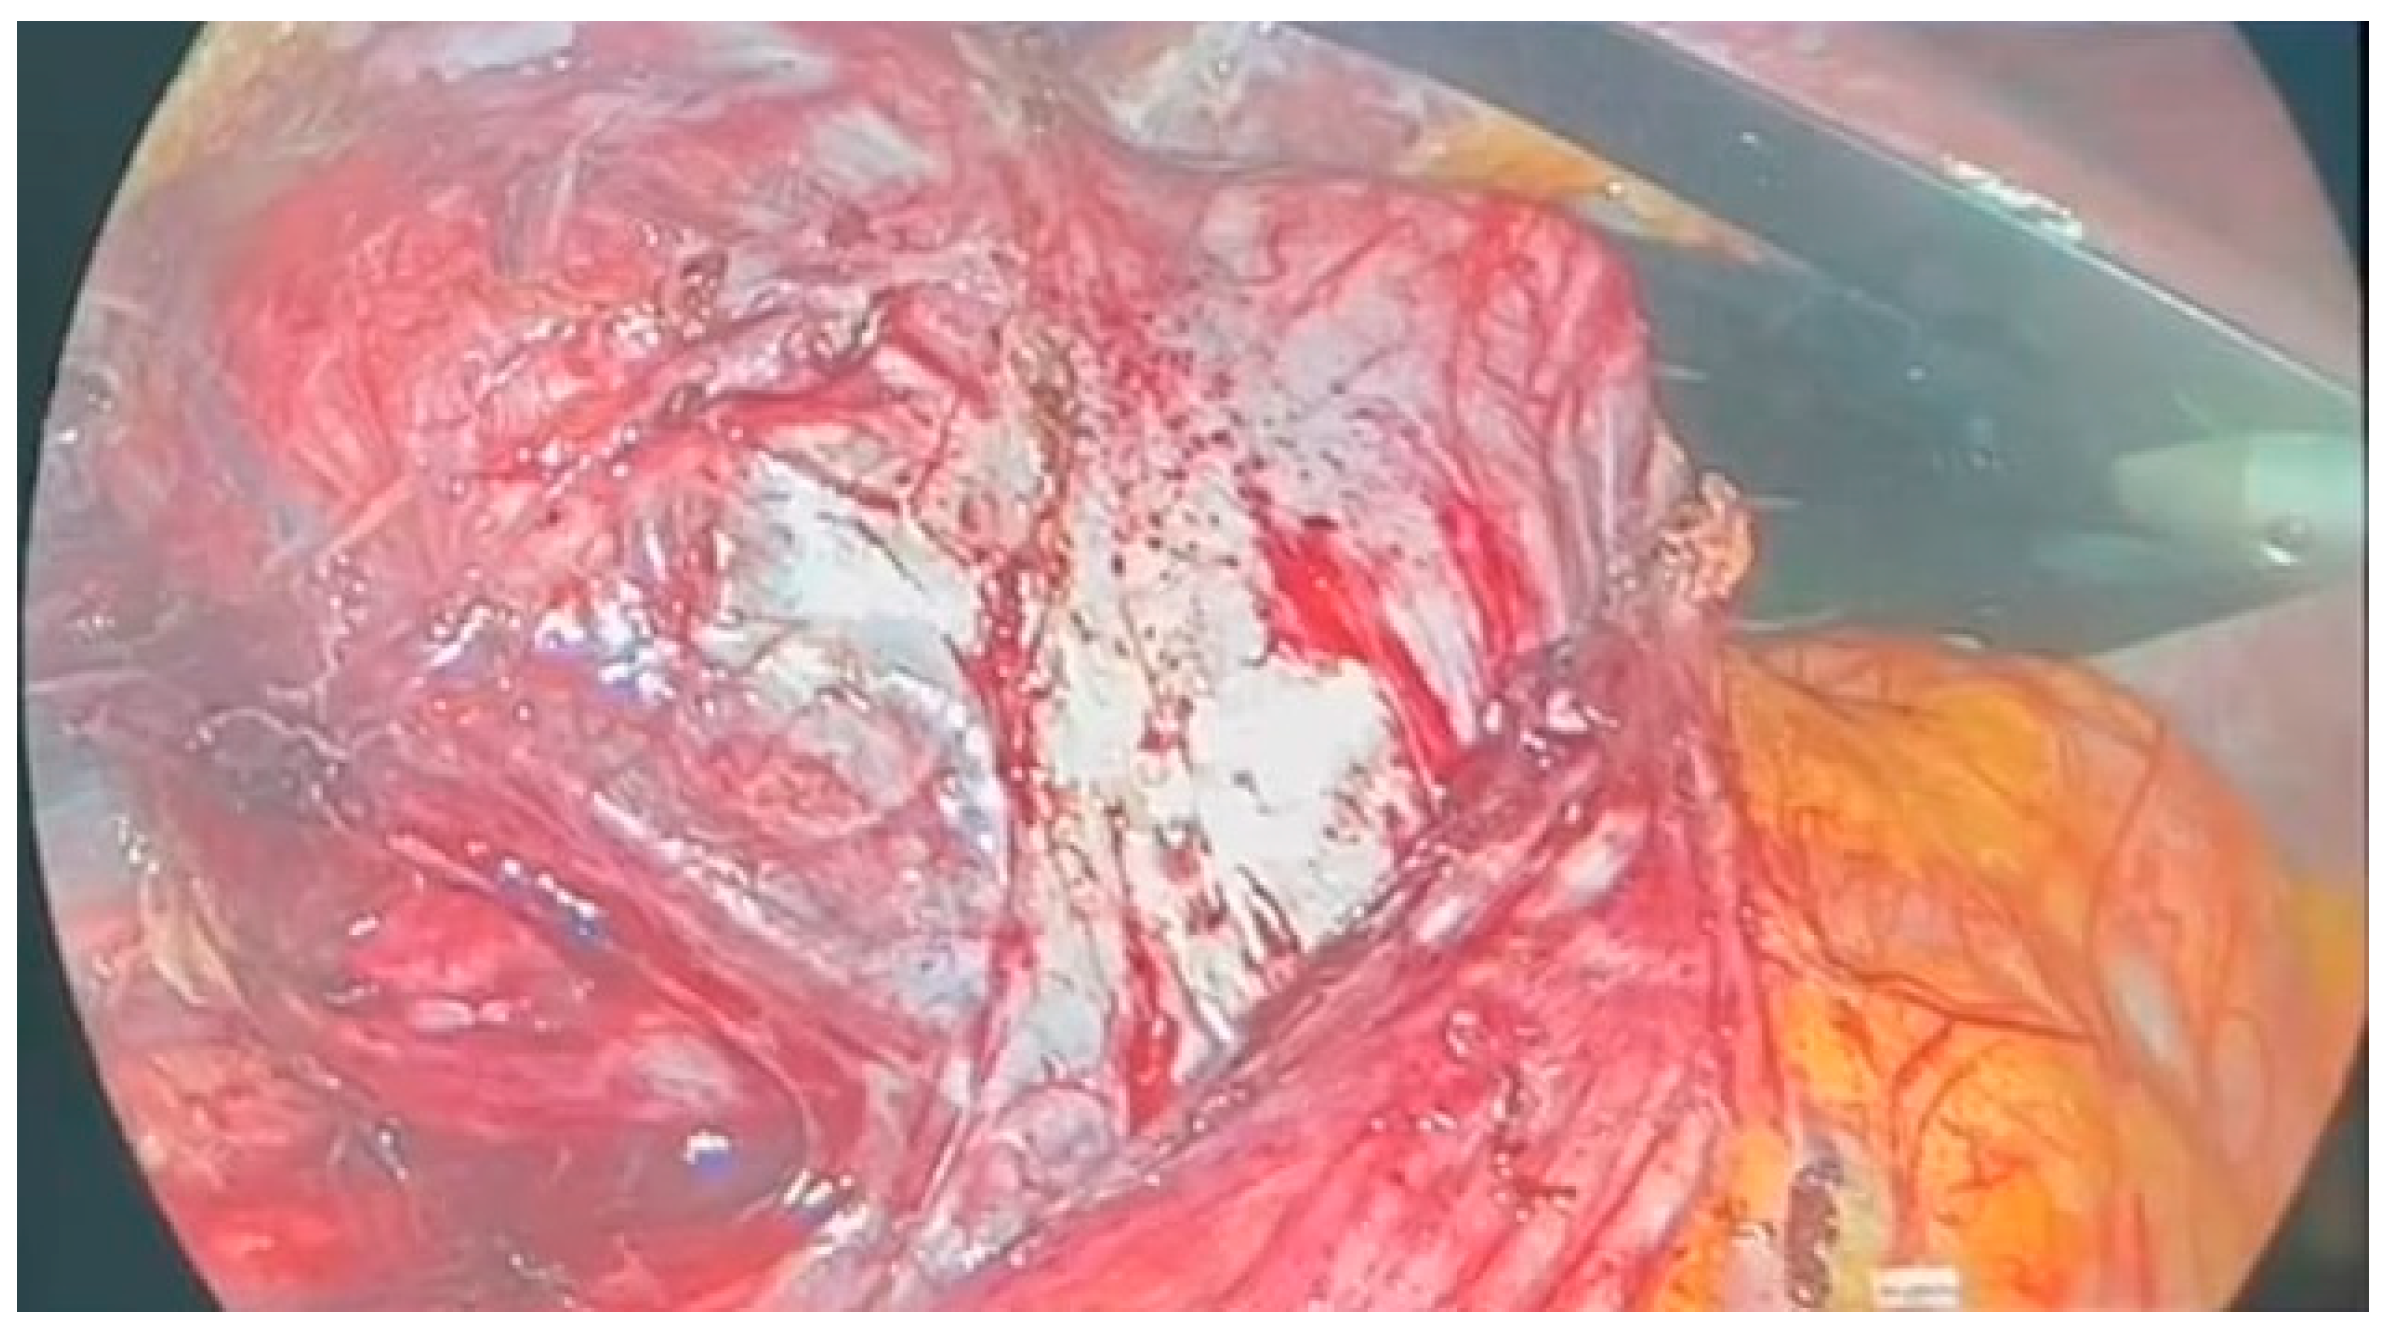

Following multidisciplinary evaluation, a right adrenalectomy was recommended. The laparoscopic procedure was performed under general anesthesia, with pneumoperitoneum initiated using Hasson’s trocar in the paraumbilical area. The highly vascular adrenal mass was densely adhered to the inferior vena cava, exerting external compression on the ipsilateral ureter and kidney, resulting in kidney hypotrophy and complete dislocation [Figure 2].

Figure 2.

Intraoperative adrenal mass.